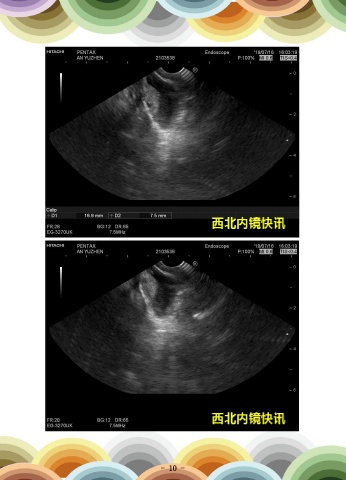

一例穿刺后血肿形成

患者男,66岁,因“胰头增大”就诊。超声内镜示:胰头占位并假囊肿形成并胰管

扩张